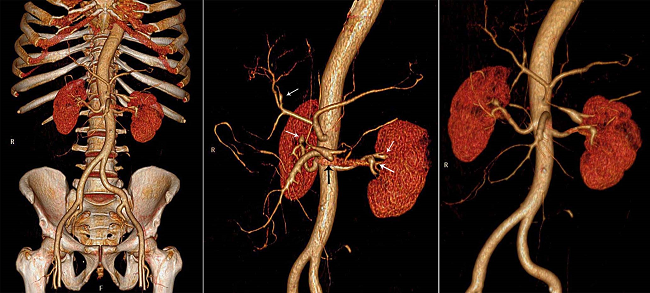

A 61-year-old Caucasian man sought medical care complaining of colicky hypogastric pain accompanied by nausea and hyperdefecation over the past 2 days. The initial clinical evaluation was unremarkable except for mild hypertension. The patient denied any previous diagnosis, but was a tobacco smoker of 10 packs/year. The clinical complaint worsened in the hours after admission with vomiting and fever despite the administration of painkillers, scopolamine, and metoclopramide concomitant with the rise in blood pressure. A few hours after admission, the patient presented a decreased level of consciousness accompanied by cold extremities, tachycardia, and severe hypotension (blood pressure of 50/30 mmHg). The cardiac, pulmonary examination results were average, but the abdomen was diffusely tender, and a crural hernia was easily reducible. Rectal examination was normal, and the patients' clinical status improved with saline volume resuscitation. Laboratory work-up showed normocytic normochromic anemia (hemoglobin: 7.8 g/dL; reference value [RV]: 13-15 g/dL), a normal remaining blood cell count, hyperglycemia (glucose: 276 mg/dL; RV: < 100 mg/dL), prolonged prothrombin time (INR = 1.69; RV: 1.0), and metabolic acidosis (pH = 7.26 with HCO3 = 12 mEq/L; RV: 14 mEq/L). Electrolytes, renal function tests, amylase, lipase, liver enzymes, and myocardium necrosis markers were normal. The electrocardiogram showed sinus tachycardia. The multidetector abdominal computed tomography showed, in the arterial phase, the presence of a hyperattenuating fluid in the epiplon retrocavity (Figure 1A) peripancreatic regions, and within the free abdominal cavity, consistent with intra-abdominal hemorrhage (Figure 1A, B). The angiographic study showed signs of small- and medium-sized vessels arteriopathy. Several branches of the celiac trunk, and the superior and inferior mesenteric arteries, showed diffuse caliber reduction, contour irregularity associated with narrowing and dilation, as well as segmental thrombosis. Saccular aneurysms were also found in the branches of both renal arteries close to the hilum and in the medium colic artery that emerged from the celiac trunk, which was most likely the origin of the hemoperitoneum. Active bleeding signs were not identified during the tomographic examination (Figure 1C, D; Figure 2).